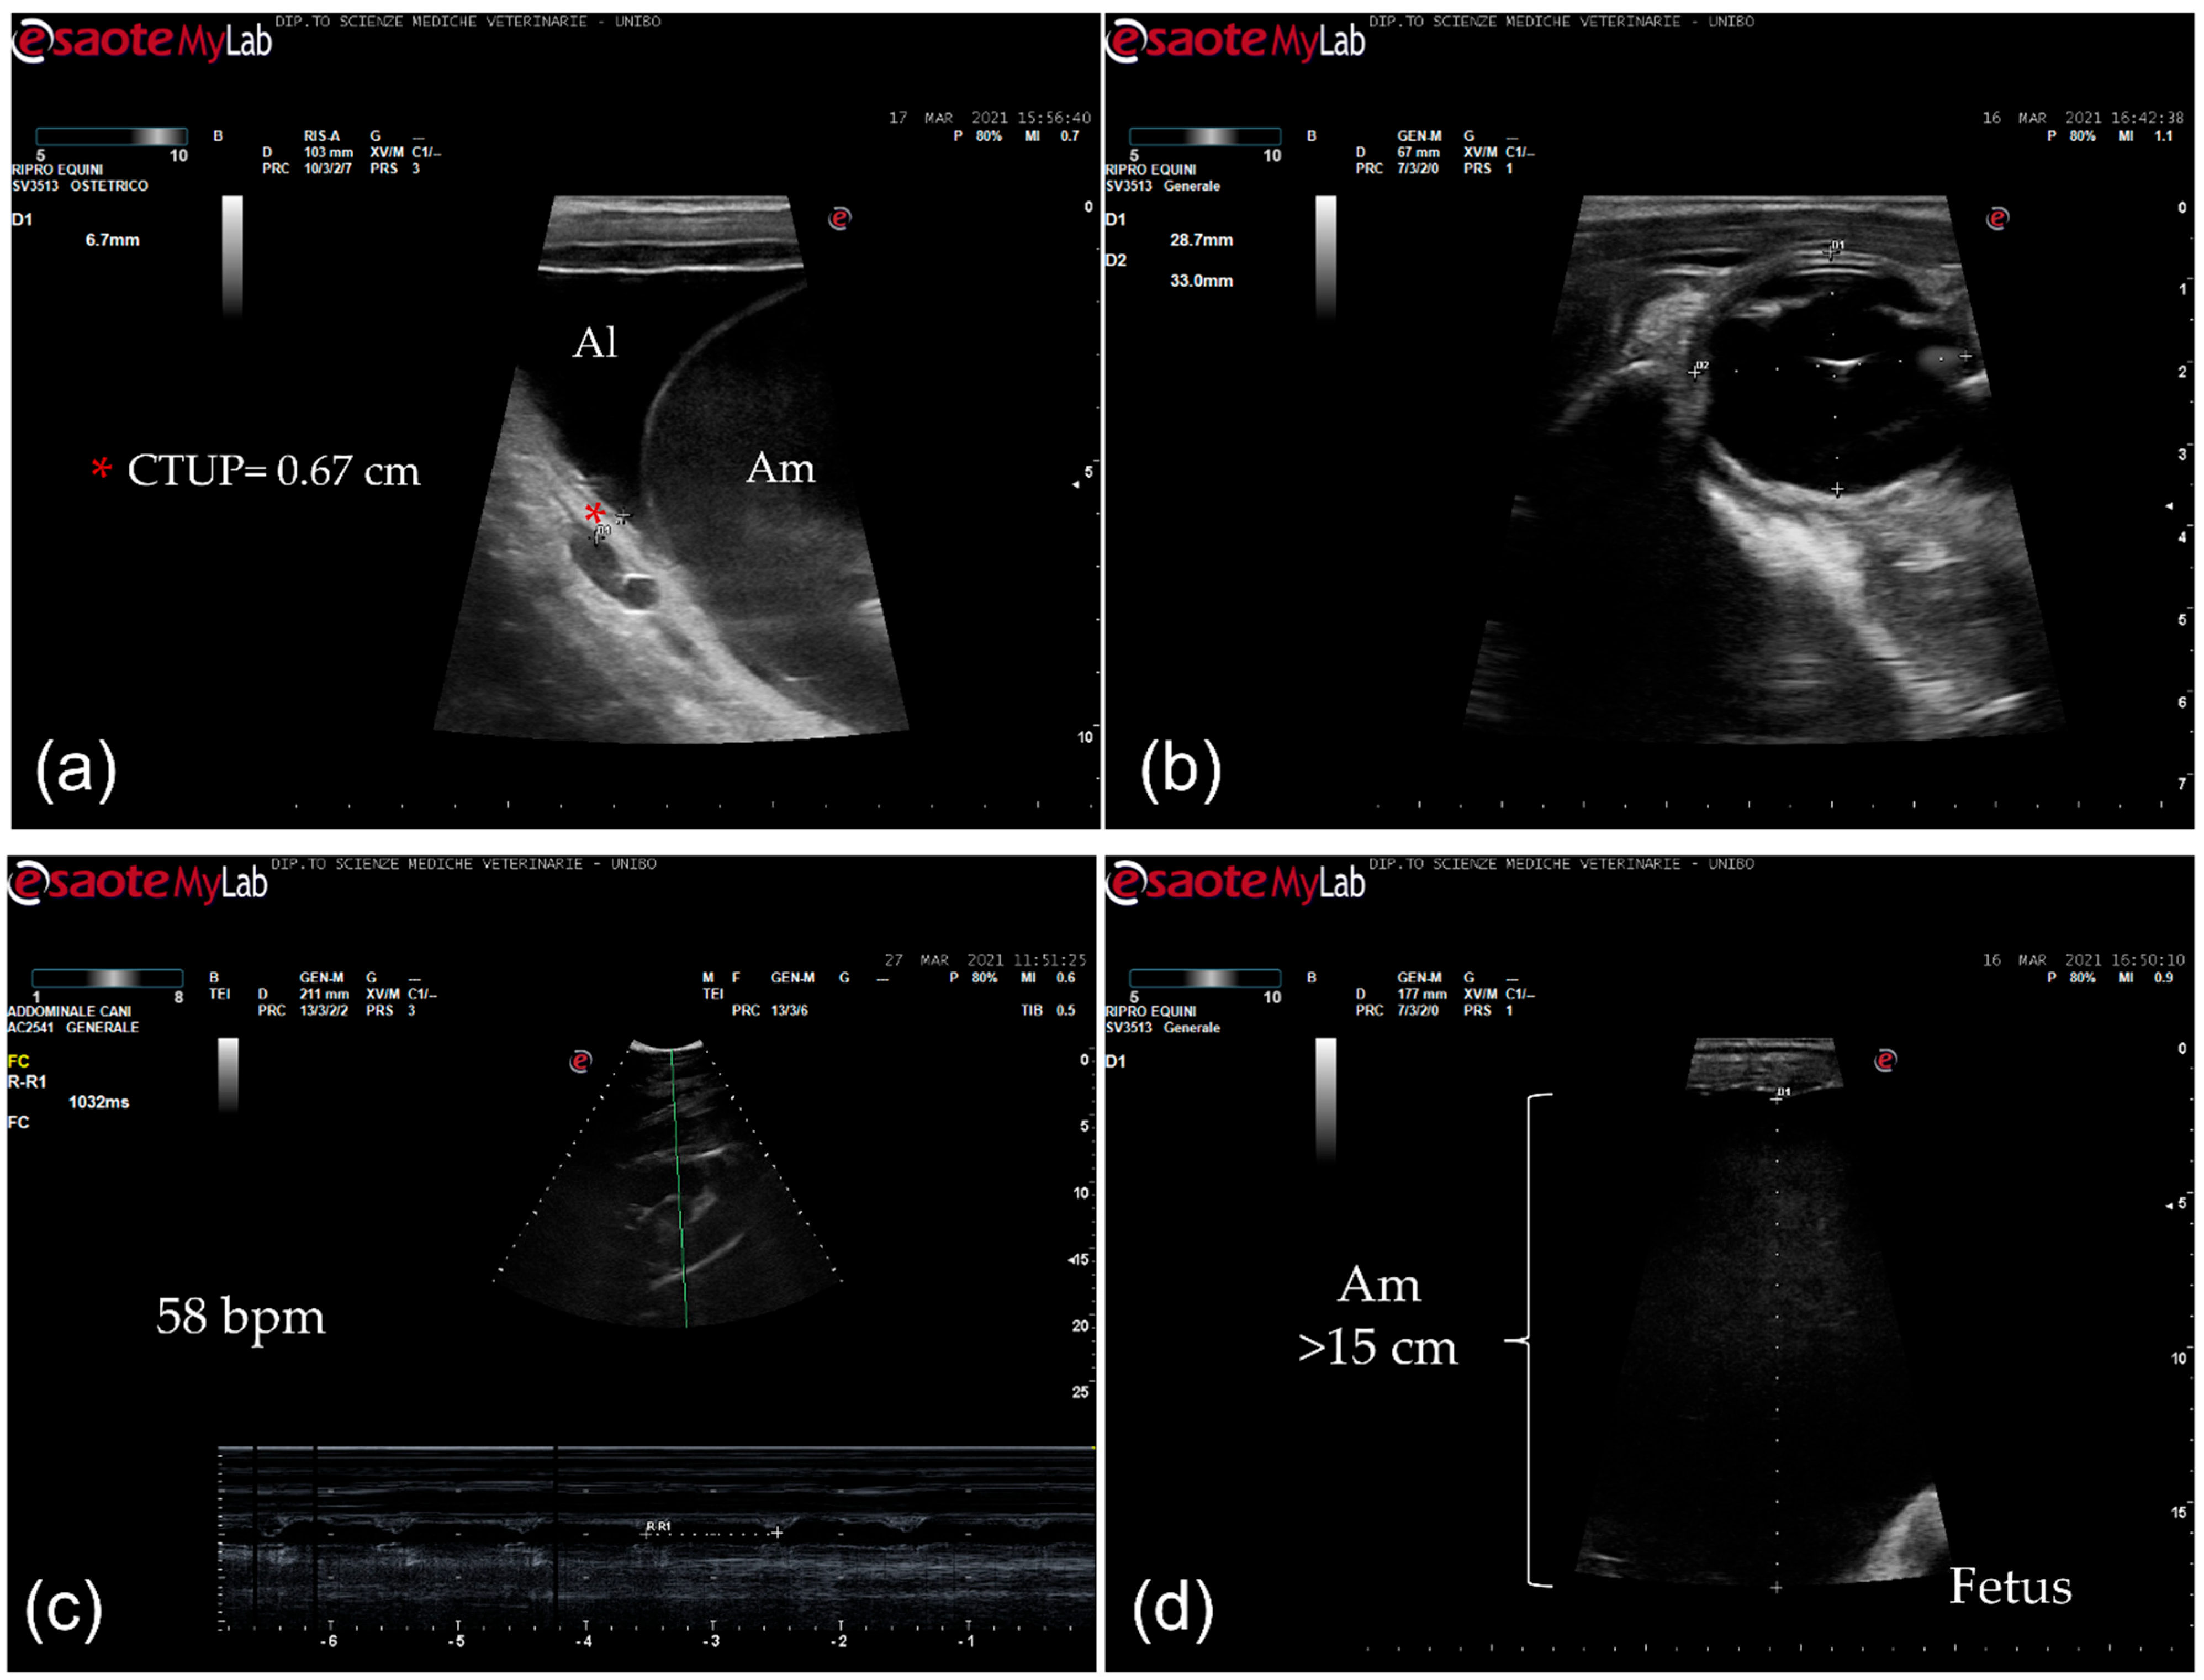

The mare had never shown any problems in the previous seven pregnancies. At admission, the mare presented with severe edema of the ventral portion of the abdomen and caudally to the udder. The mare was reluctant to move and sweaty. Body condition score and muscular tone were normal. At physical examination, she presented tachycardia (65 beats/min) and slight tachypnea (20 breaths/min), and the body temperature (37.6 °C) was within normal limits. On abdominal auscultation, the motility was decreased, and fecal output was reduced, with dry feces throughout hospitalization. The mammary gland was well developed. Mammary secretions were evaluated with a calcium titration method (FoalWatch; Chemetrics, Midland, VA, USA) and the concentration of calcium was 150 ppm Ca [11]. Hemato-chemistry parameters were within normal limits and the serum biochemistry was monitored during the hospitalization period. Transrectal ultrasonographic (US) examination showed a combined thickness of the utero-placental unit (CTUP) within normal limits (range 5.53–6.77 mm at 10 months of pregnancy) (Figure 1a) [12]. The fetus was in anterior presentation, and the orbital size was 33 × 28.7 mm (Figure 1b). Transabdominal ultrasonographic examination showed a fetal heart rate at rest at the lower limit (58 bpm) (Figure 1c) and lower than the normal range after activity (67–71 bpm) [13,14]. The maximum depth of the amniotic fluid was measured in the mid-caudal quadrant (>15 cm; Figure 1d); in the mid–mid quadrant, the allantoic fluid was measured at the maximal depth (11 cm) [14].

Figure 1. Ultrasonographic images. (a) Transrectal ultrasonographic examination of the combined thickness of the uterus and placenta (CTUP) (red asterisk); Al: allantoic fluid; Am: amniotic fluid; (b) fetal orbit measurement (transrectal ultrasonography); (c) fetal heart rate measurement (58 bpm) (transabdominal ultrasonography); (d) depth of the amniotic fluid (>15 cm) (transabdominal ultrasonography); Am: amniotic fluid.